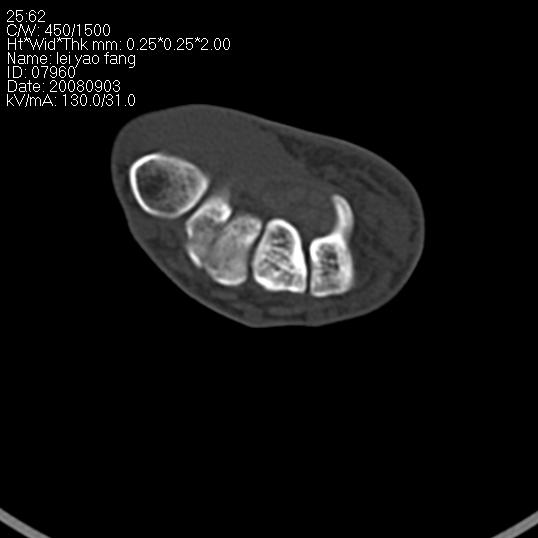

以下是引用杀毒软件在2008-9-4 17:41:00的发言:[br]考虑----舟骨囊肿